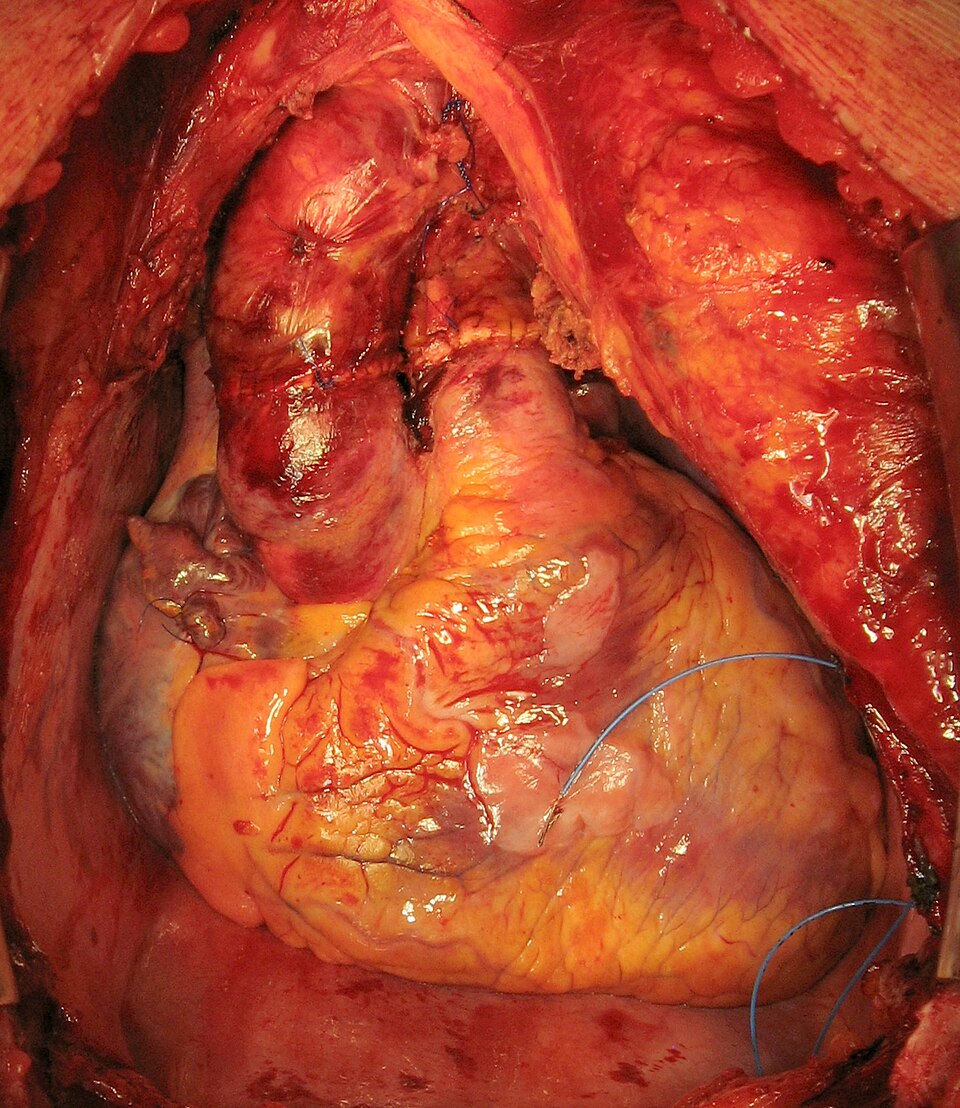

Heart Transplantation

The clash between life and death is starkest in heart transplantation, where the decision to replace a failing heart with a donor's is a battle against time and biology. Heart transplantation is not just a...